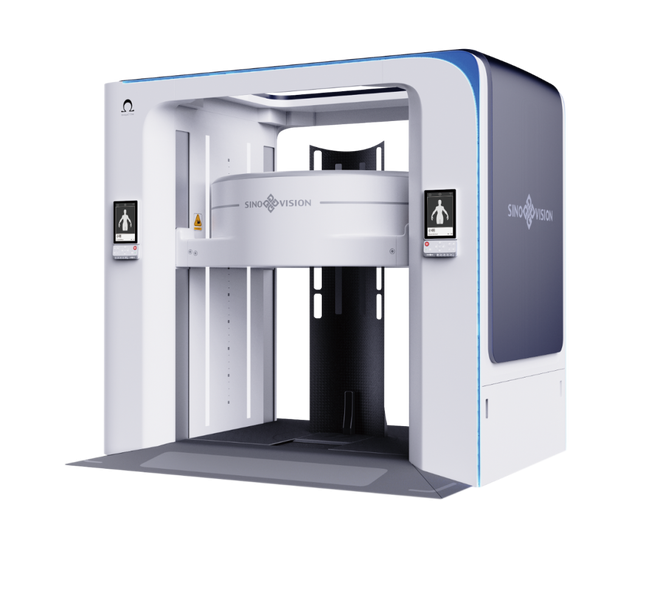

全球首台超大孔径站立位CT

项目类型

器械质押区

起投金额

7000USDT

每日释放:0.8

释放周期:135 天

已购: 11428

剩余: 0

OmegaCT One天境CT

项目类型

器械质押区

起投金额

18000USDT

每日释放:0.9

释放周期:150 天

已购: 8333

剩余: 0